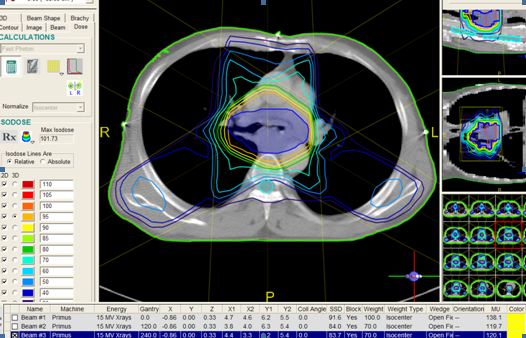

- Chụp CT mô phỏng cấp cứu, sau đó lập kế hoạch xạ trị ngay .

- Liều xạ trị với máy gia tốc tuyến tính: 3 Gy/ngày x 10 ngày, mức E 15 MV

- Ngày hôm sau: Tiến hành hóa trị đồng thời với Cisplatin - Docetaxel.

| Hình ảnh lập kế hoạch xạ trị cấp u phổi chèn ép khí phế quản bằng máy gia tốc |

|

| Biểu đồ liều - thể tích (DVH): Liều tại u đạt gần 100%, trong khi cơ quan lành như tủy sống, phổi lành vẫn ở giới hạn thấp, an toàn. |